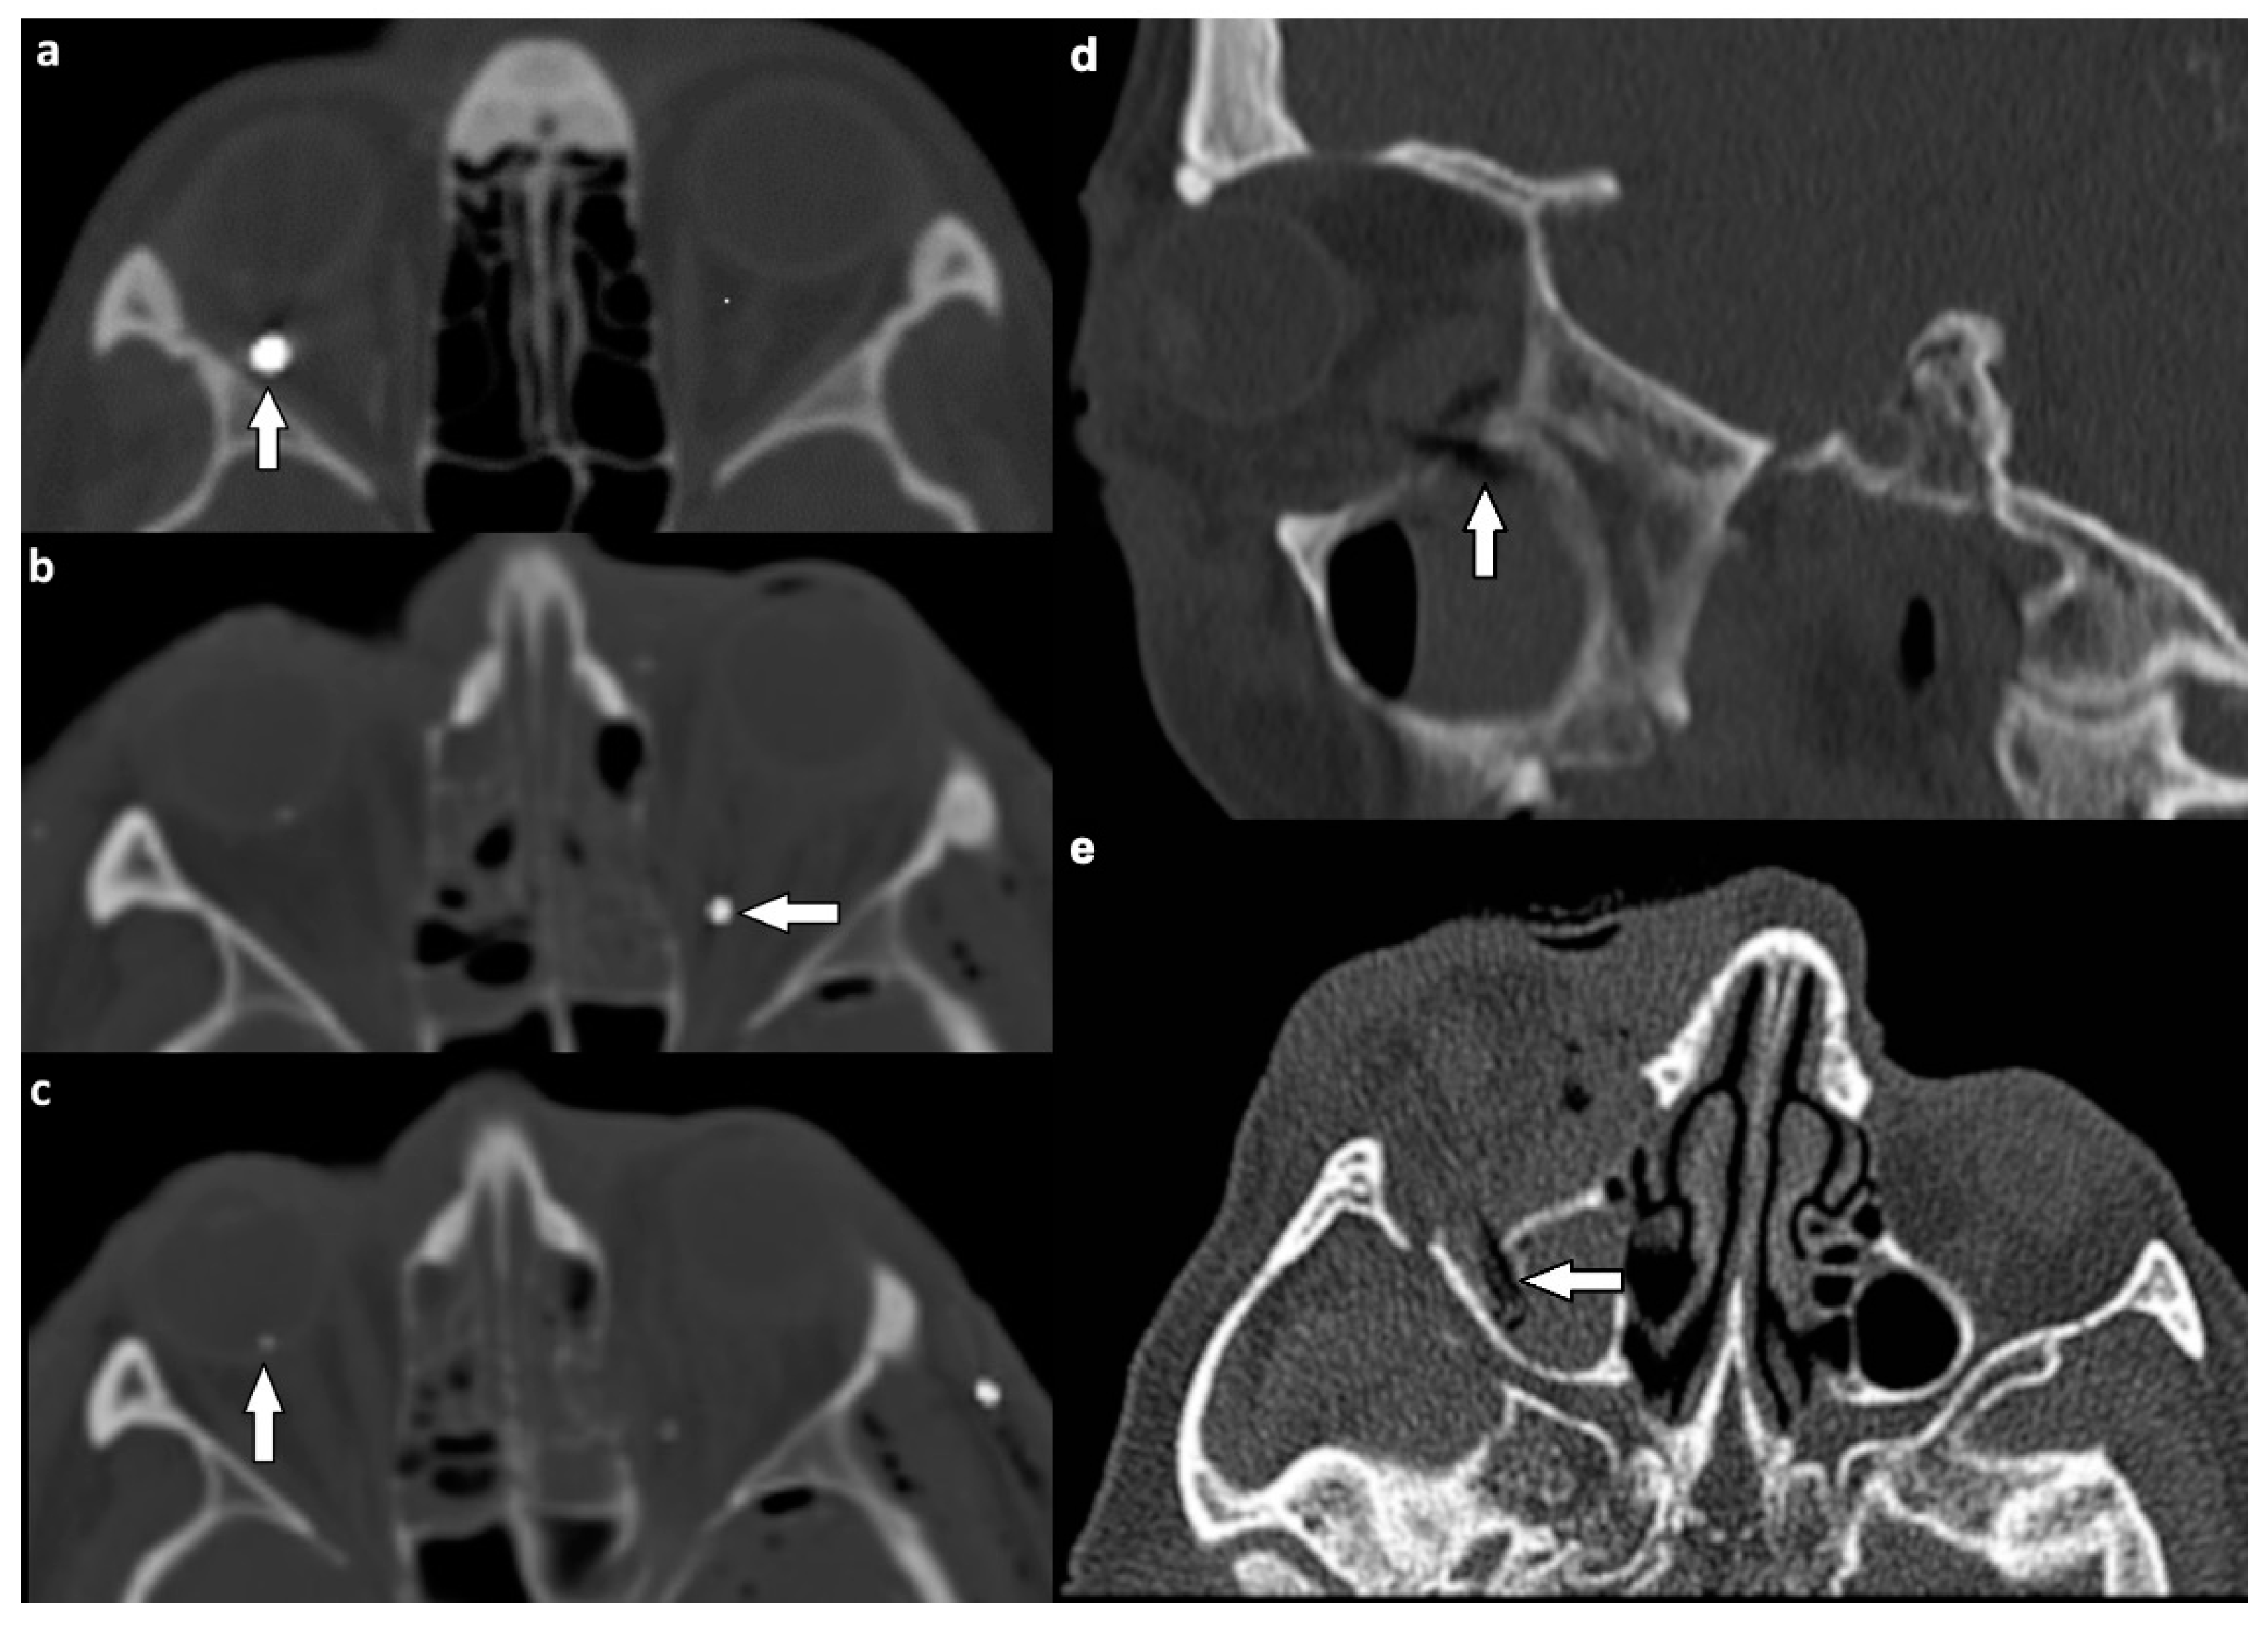

| Extraocular muscles | 54 (53.5) | |

| dislocation | 45 (44.6) | |

| pierced by bone fragment | 8 (7.9) | |

| intramuscular foreign body | 1 (1.0) | |

| Optic nerve | 24 (23.8) | |

| elongation | 13 (12.9) | |

| otherwise altered morphology | 10 (9.9) | |

| pierced by foreign body | 1 (1.0) | |